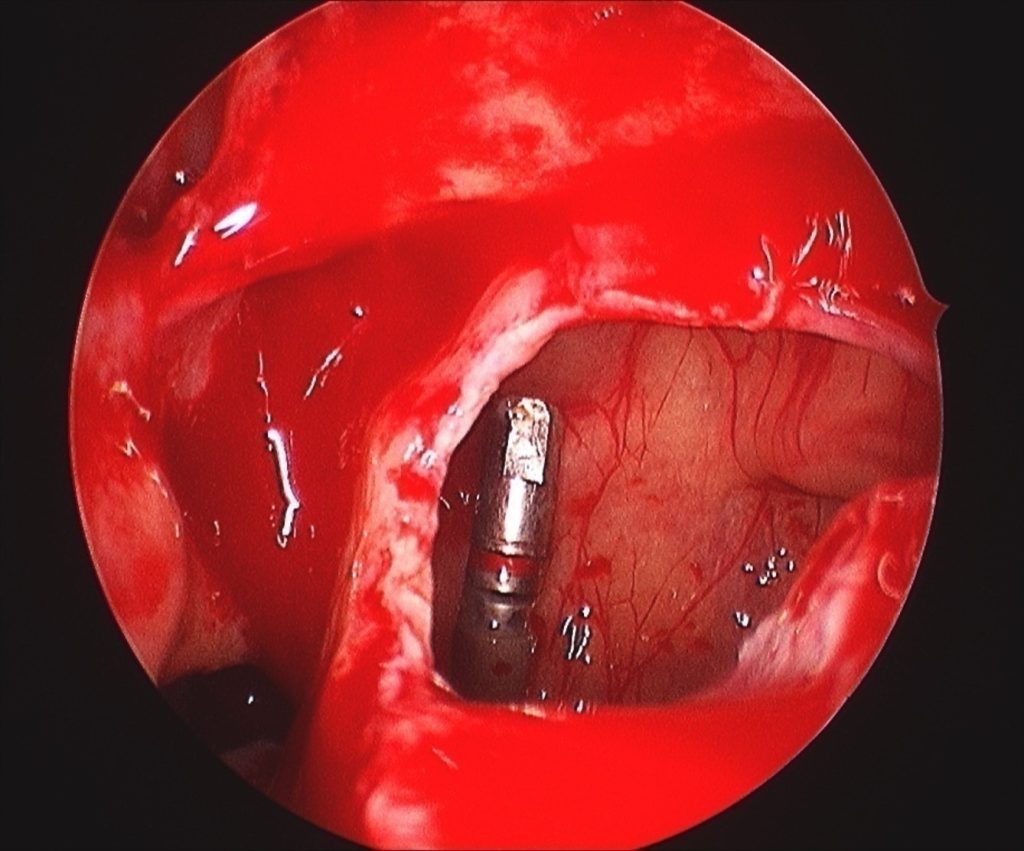

In Figure 2 the maxillary sinus is opaque (infected) due to chronic sinusitis before surgery. This resulted in infection of the zygoma implant and the patient presented with pus discharging through the skin over the zygoma area. The zygoma implant is described as running between the sinus bone and its mucosa, however when this area is infected, a drainage route is created when the bone is perforated and the sinus mucosa is infected and fragile. In this case the infection was drained by FESS and once sinus ventilation was re-established, the infection settled and we managed to preserve the zygoma implant.